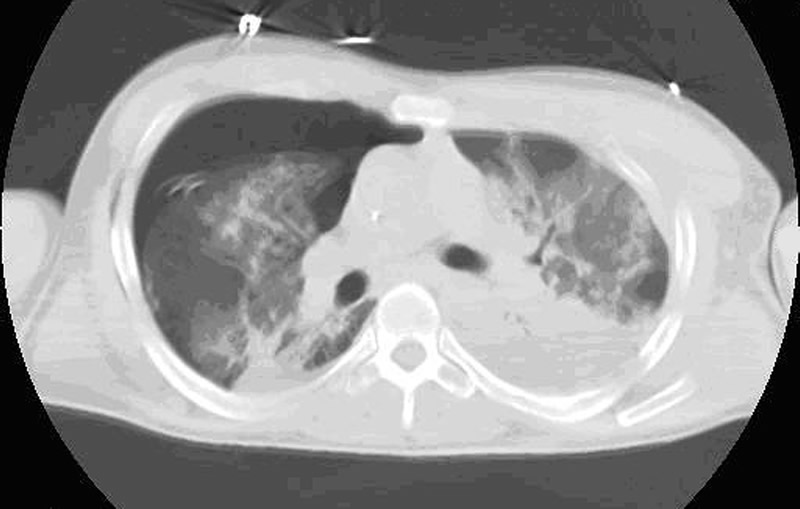

Although surgical management of patients with severe flail chest is at present controversial, we think that surgical stabilization is strongly indicated in specific clinical situations. The effectiveness and the ideal timing of chest wall stabilization in patients on mechanical ventilation is related to the degree of the pulmonary parenchymal damage [7,8]. The presence of extensive pulmonary contusion (Figure 1) is a relative contraindication to surgical stabilization. These patients require prolonged ventilation, and an early surgical stabilization would not provide benefit [7,8]. However, a surgical procedure can be proposed if the patient fails to wean from the ventilator once a partial resolution of pulmonary contusion is achieved [9,10].

Figure Figure

Figure 1. Blunt chest trauma with left flail chest and ipsilateral severe pulmonary contusion and posttraumtic pneumothorax on the right. Figure 2. Blunt chest trauma with right flail chest with ipsilateral pleural effusion and mild pulmonary atelectasis